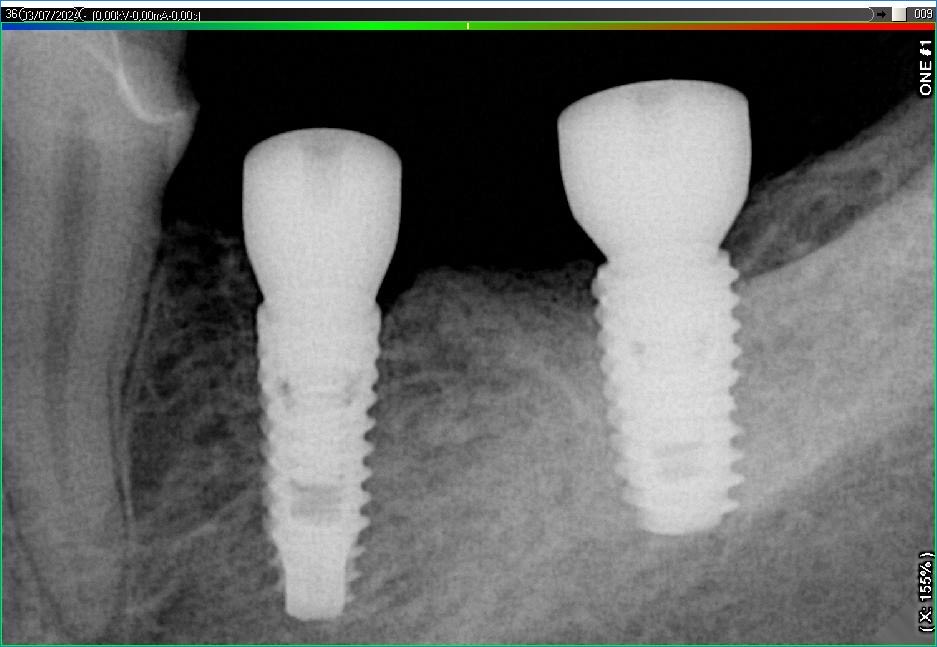

Імплантація